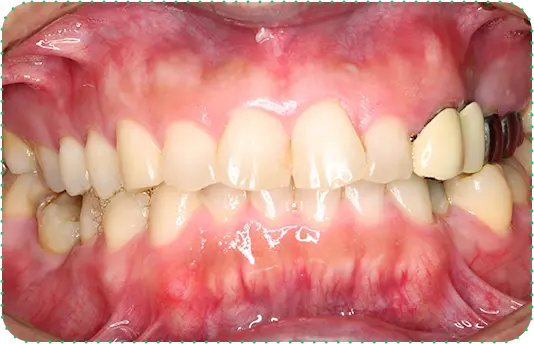

Before

After

主訴

前歯をきれいにしたい

治療期間

8か月

治療費

40万円

治療内容

右上2番をマウスピース矯正で移動してラミネートべニアにて修復

治療のリスク

【マウスピース】

矯正装置を初めて装着した時は、違和感や圧迫感、疼痛などを感じる場合があります。

歯根吸収や歯肉の退縮が起こる場合があります。

1日の装着時間が長いため、口内清掃不足だとむし歯・歯周病のリスクが高くなります。

歯の移動後に保定装置(リテーナー)の使用が不十分の際は、後戻りが生じる場合があります。

マウスピースの装着時間が少ないと治療期間が長引く場合があります。

【セラミック】

咬み合わせによっては、セラミックが欠ける可能性があります。